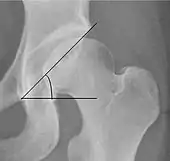

- (D) The acetabular index measures the acetabular roof slope. It is the most useful measure of acetabular dysplasia until 6 years of age. It is formed between Hilgenreiner line and the acetabular roof. In newborns, values of in males and in females are considered normal. It normally decreases with age: